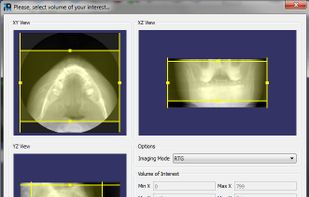

OsiriX is an image processing software dedicated to DICOM images (".dcm" / ".DCM" extension) produced by imaging equipment (MRI, CT, PET, PET-CT, SPECT-CT, Ultrasounds, ...). It is fully compliant with the DICOM standard for image comunication and image file...